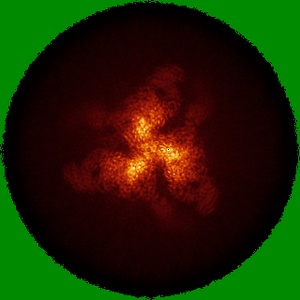

Cryo-EM structure of HIV-1 BG505 SOSIP.664 Env bound to 3-sCD4, 3-VRC34.01 Fab with one gp120 rotated, Population 4

Conformational trajectory of the HIV-1 fusion peptide during CD4-induced envelope opening.

Thakur B, Katte RH , Xu W , Janowska K, Sammour S, Henderson R , Lu M, Kwong PD , Acharya P

(2025) Nat Commun , 16 , 4595 - 4595